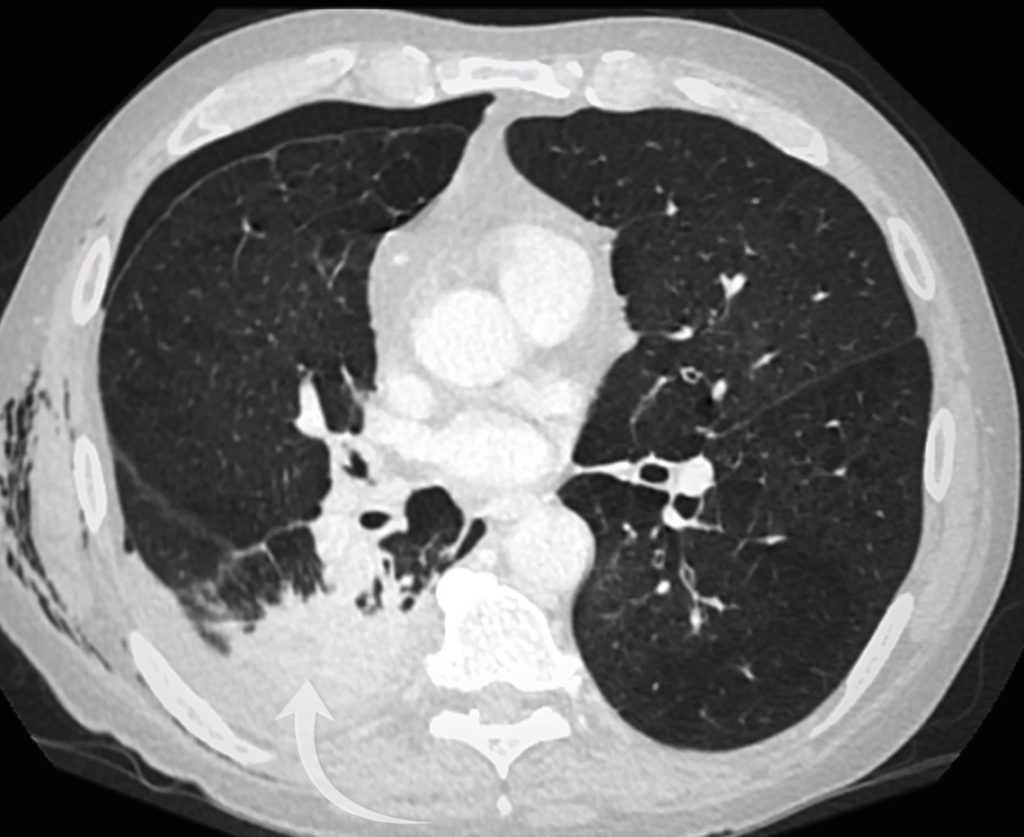

CT scan review

A chest drain was inserted, but the patient’s breathlessness didn’t improve, a red flag suggesting the drain might not be in the right place. Now have a look at the CT scan in this case.

• The chest drain is in the chest wall, not in the pleural space, explaining why the pneumothorax persists.

• There is severe emphysema and a small right pleural effusion.

• The two lung opacities are confirmed:

• One in the apical right lower lobe (corresponding to the opacity behind the hilum).

• One in the right upper lobe.

The chest drain is out side of the pleura (bottom arrow) and the pneumothorax persists (top arrow). There is a small right pleural effusion.

CT confirms a right upper lobe opacity accounting for the right mid zone opacity on chest X-Ray.

A right lower lobe opacity accounts for the opacity seen overlying the right hilum on chest X-Ray.

Spiculation

Examining the right upper lobe lesion in more detail, we see small spicules radiating from it. A spiculated lesion raises concern for a primary lung cancer. In my experience however you need to adopt a little caution when the underlying lung is abnormal as with severe emphysema a lot of lesions can look spiculated!

The right upper lobe lesion is spiculated.